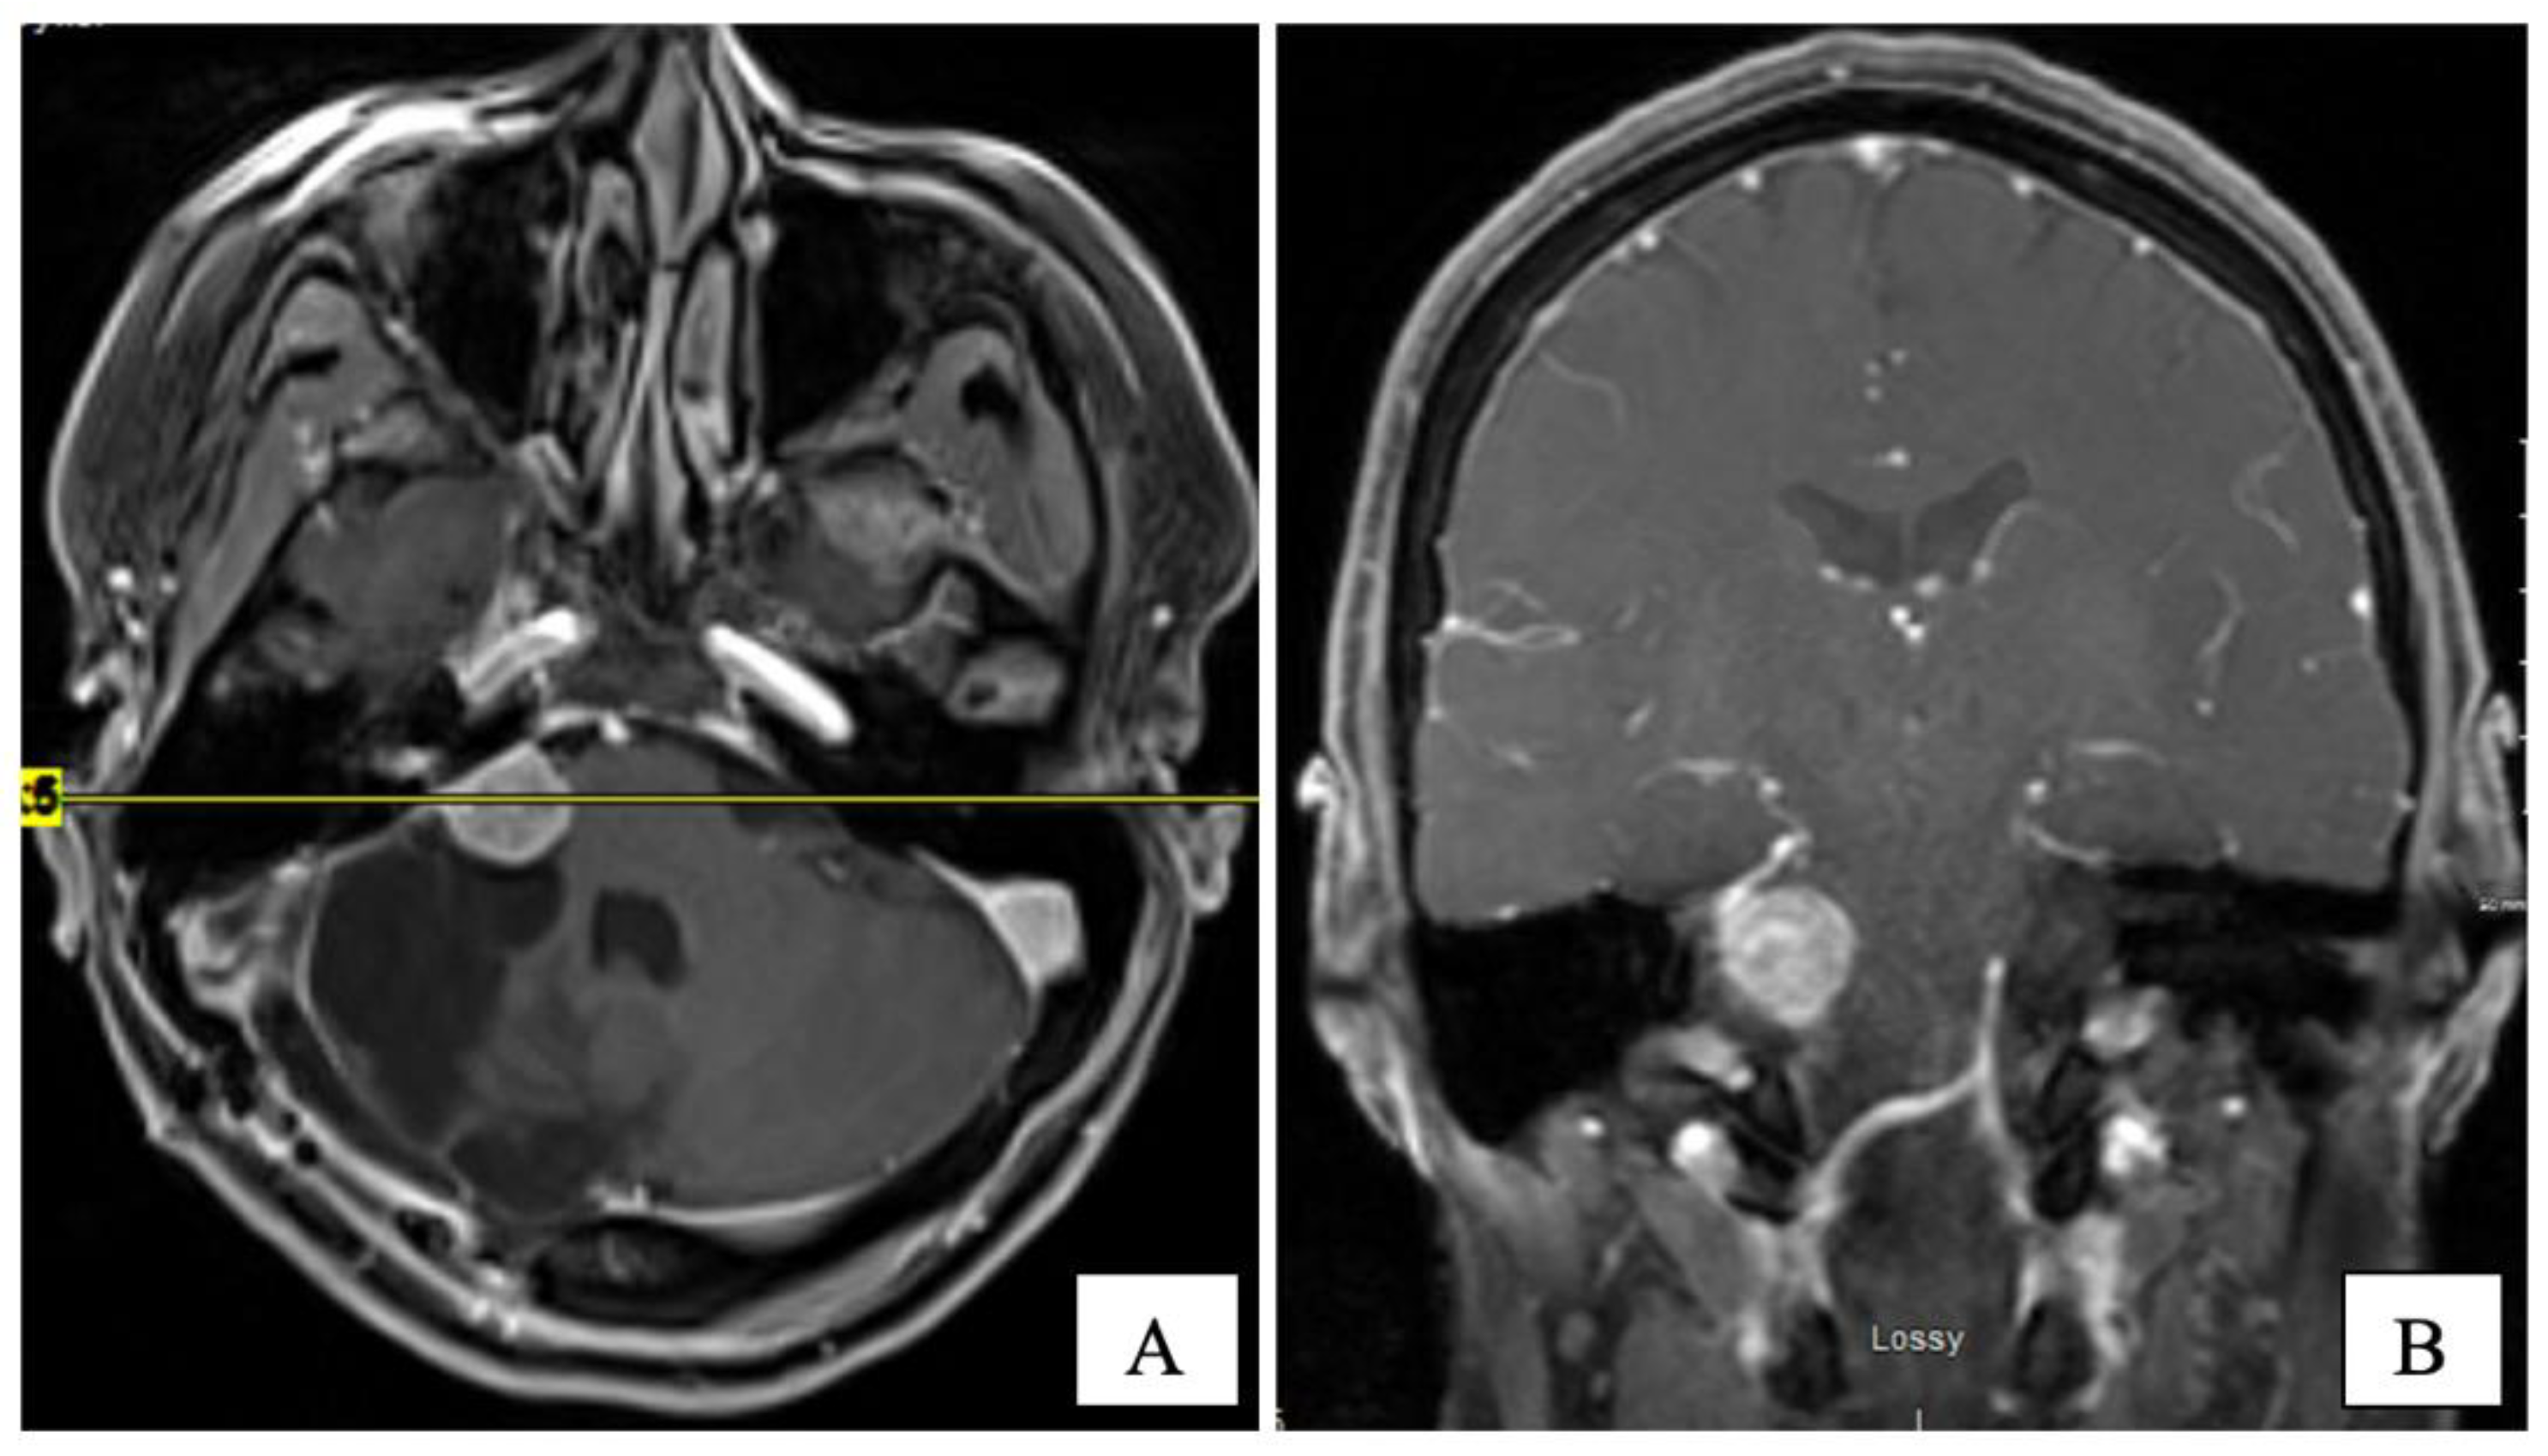

Several years later, in mid-2015, she presented with headaches, worsening ataxia, and new-onset facial palsy. Her physical exam revealed asymmetric pupils (right 5 mm and left 3 mm), reactive to light with a horizontal beat (gaze-evoked), nystagmus, and diplopia on lateral gaze. She had right-side hearing loss and an absent gag reflex. A new MRI revealed the residual tumour’s progression (14 × 14 × 17 mm) with central cystic degeneration/necrosis. The tumour extended further into the right internal auditory canal, causing a mild mass effect on the brainstem. The patient was reluctant to consider further surgical intervention. Three subsequent MRIs performed in 2015 demonstrated the continued slow growth of the residual tumour (Figure 3).

Figure 3. T1-W post-gadolinium MRI at 7 years post-op on axial (A) and coronal (B) planes. The CPA tumour measured 16 × 15 × 17 mm.